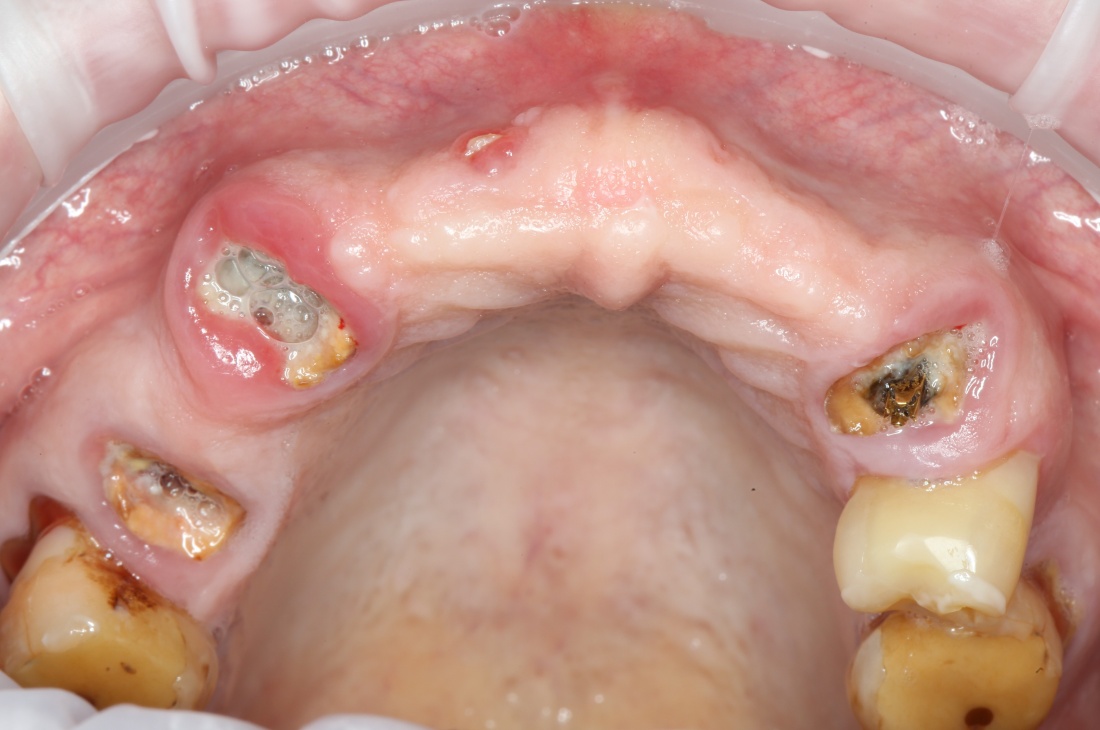

Вот клиническая картина через 4 месяца после ранее проведенной имплантации с остеопластикой:

Как видишь, коллеги из недалекой дружественной страны не осилили снятие швов. Мне это не нравится, хотя и объясняет, почему люди готовы ехать за тыщи километров ради 20-минутной операции удаления зуба мудрости.

Ну хорошо. Швы сняли. Делаем разрез. Обрати внимание, что после всех проведенных операций у нас остается очень небольшой по ширине слой жевательной слизистой оболочки: